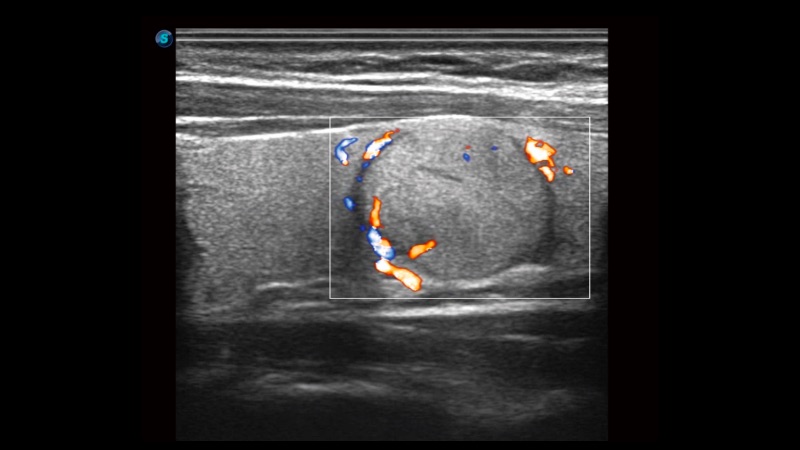

高分辨率血流成像技术提高了对低速血流信号的检测能力。在提高空间分辨率的同时,也克服了血流外溢现象,为用户提供更加真实的血流动力学信息。